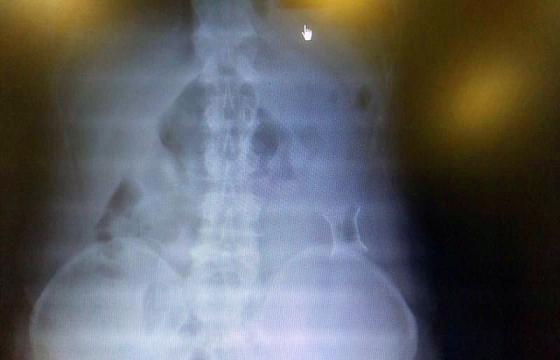

受試患者在結腸端端吻合術中,使用我司新研制產品達到了理想的預期效果。患者術后7天、14X光片顯影,可降解腸道支架均能按研制設計的預期時間節點保持應有強度,術后21X光片顯示可降解腸道支架已完全破碎,并排出體外。在整個試驗過程中,病患無任何不良反映,耐受良好。